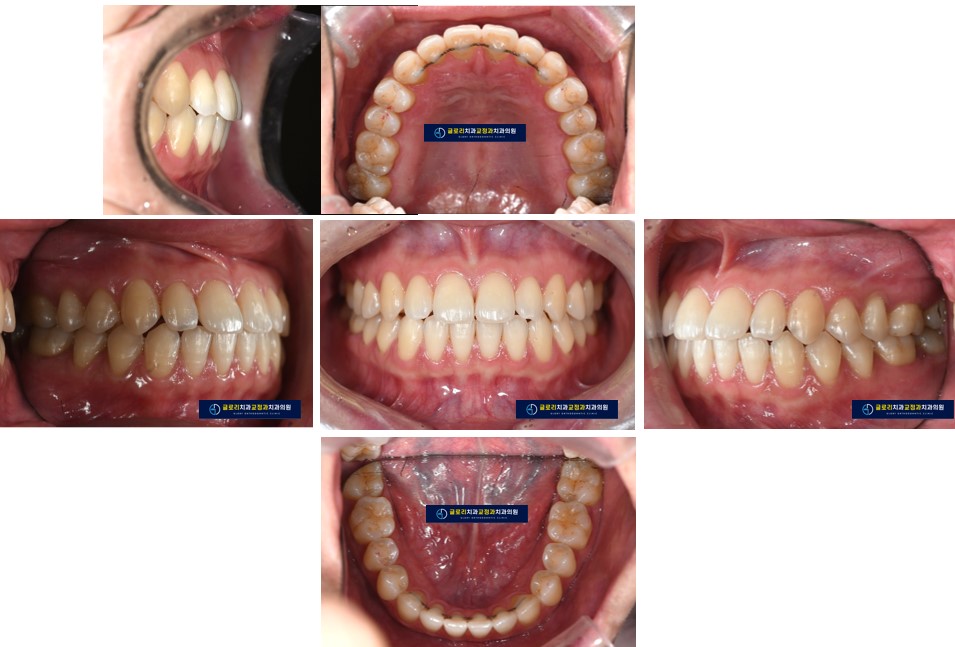

다음 사진과 같이 치아 안쪽으로 보이지 않게 유지장치를 부착하여

공간이 재발하지 않도록 유지 관리를 잘 해야 합니다.​

이렇게 오랫동안 존재하던 공간을 닫은 경우는 지속적인 유지 관리가 매우 중요합니다.

다시 공간이 생기는 방향으로 되돌아갈 수 있기 때문입니다.